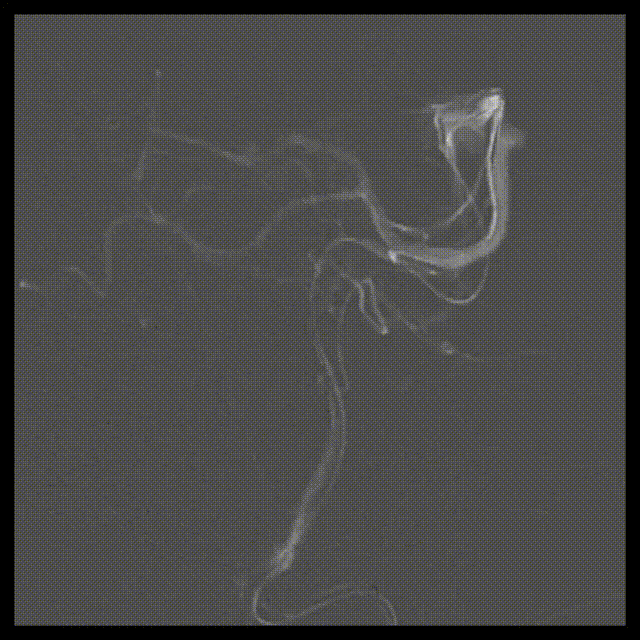

入院后立即行脑血管造影提示椎基底冗长扩张(基底动脉脑桥部分最宽处约5.2mm),伴有基底动脉多发动脉瘤,基底动脉尖动脉瘤(最大径约8mm)伴子囊和基底动脉下段动脉瘤(最大径约11mm)(图2)。

A

B

C

D

E